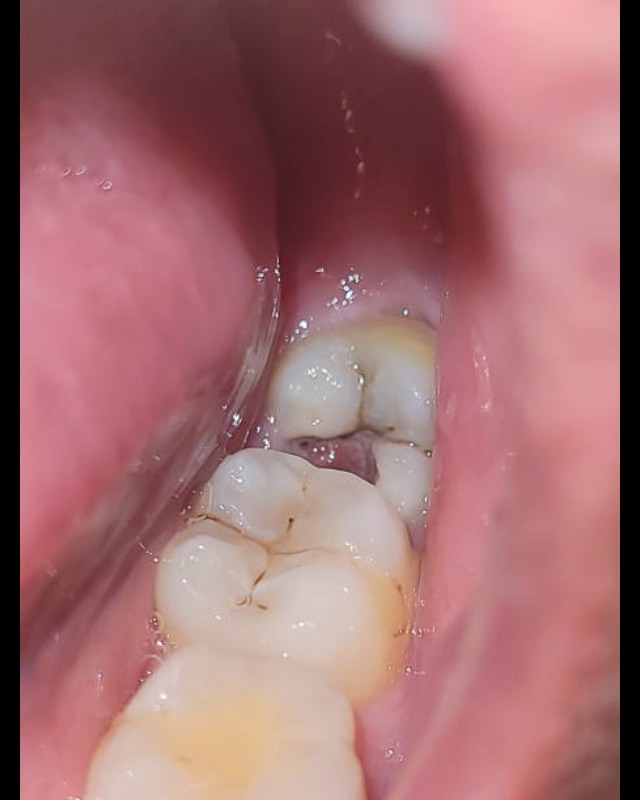

An impaction of the third molar, commonly known as an impacted wisdom tooth, occurs when the tooth fails to erupt fully into its normal functional position because it is blocked by another tooth, bone, or soft tissue. The primary cause is a mismatch between the size of the teeth and the available space in the jaw.While some impacted teeth remain asymptomatic, many cause significant issues: Pain and Swelling: Localized discomfort, jaw stiffness, and facial swelling., Pericoronitis: Inflammation and infection of the gum flap covering a partially erupted tooth., Tooth Decay: Impacted teeth are difficult to clean, making them and the adjacent teeth prone to cavities., Cysts and Tumors: In rare cases, the sac around the tooth can fill with fluid, potentially damaging the jawbone and nerves. Treatment Options Watchful Waiting: If the tooth is completely buried, asymptomatic, and disease-free, a dentist may monitor it with regular X-rays from sources like the NHS. Extraction: The most common treatment involves surgical removal, often recommended for teeth causing pain or infection. Coronectomy: Removing only the crown while leaving the roots to protect a nearby nerve. Best Dental Clinic in Santhosapuram Best Dental Surgeon in madambakkam Best tooth removal procedure in Gowrivakkam Best Wisdom tooth removal in Sembakkam Best Dental clinic in Kovilambakkam Best wisdom tooth removal in Medavakkam